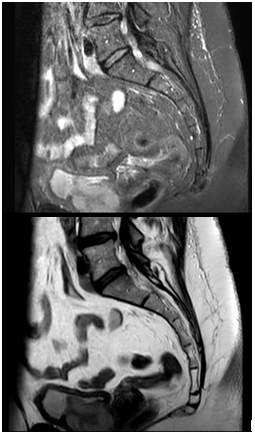

Given this finding, an urodynamic study (UDS) was performed and showed an increased sensibility associated with involuntary detrusor contractions and lower urinary tract obstruction (Figure. 1). Pelvic MRI revealed a solid mass depending on the urethra causing stricture (Figure. 2) and the CT scan identified a heterogeneous 7x6cm mass around the urethra that infiltrated the posterior bladder wall (Figure. 3). Cystoscopy allowed the visualization of membranous tissue with fibrotic aspect on the urethra and a normal bladder without tumors. Biopsies were taken in the same procedure and urine cytology. Results were inconclusive but suggested urethral clear cell carcinoma, therefore it was discussed in a multidisciplinary committee formed by urologists, oncologists, radiologists, nuclear radiologists, and radiotherapists in which radical surgery with curative means was decided.

Figure 2 Pelvic MRI A) STIR (Short-TI Inversion Recovery). Thickened bladder wall with paraurethral solid mass marked with two asterisks. B) Same image in T2.